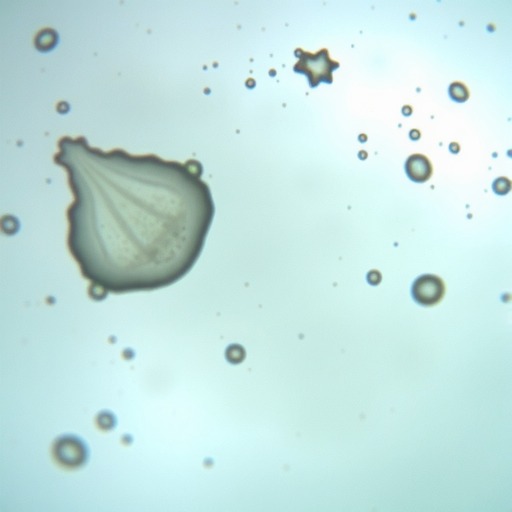

4.脓肿及异物超声征象;

5.如何超声引导取出异物。